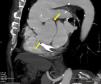

Valsalva sinus pseudoaneurysms are uncommon. The main causes for the formation of pseudoaneurysms are endocarditis, previous enlargement of the aortic root, aortic regurgitation and the use of a composite graft. We report the case of a 79-year-old man with an aortic bioprosthesis implanted five years ago to treat severe aortic regurgitation (AR) with a normal aortic root. A new diastolic murmur was heard in the last clinical review, so the patient was referred for transthoracic echocardiography, which demonstrated severe AR and a dilated aortic root. Transesophageal echocardiography (Figures 1 and 2) confirmed severe AR with an aneurysmal dilatation of the non-coronary sinus, with no signs of infection. Computed tomography (CT) confirmed severe dilatation of the aortic root (Figure 3, arrows). During surgery, a transverse fissure was detected in the intima of the non-coronary sinus. The valve was replaced with a 27-mm valve and the aortic root was remodeled using a 30-mm vascular graft.